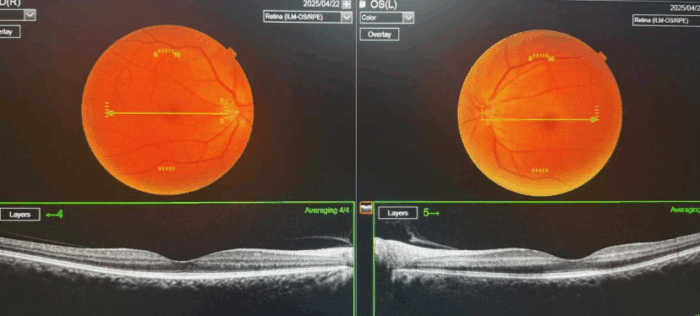

此次获救的患者突发左眼视力骤降,眼前仅能感知手动,情况万分危急,遂紧急前往万宁市人民医院就诊。海南医科大学第一附属医院派驻该院的眼科专家邢悦主治医师迅速接诊,凭借深厚专业素养与丰富临床经验,迅速判断出患者为视网膜中央动脉阻塞。

“时间就是光明!”邢悦主治医师深知每一秒都关乎患者视力存亡,立即启动绿色通道,为患者量身定制个性化综合治疗方案。抢救过程中,邢悦全程指导,争分夺秒:从及时吸氧、扩血管、降血压,到精准眼球按摩,再到积极协调血管介入科会诊,拟开展血管溶栓治疗,每个环节都严格把控、迅速操作。令人欣喜的是,在准备溶栓前,患者视力奇迹般恢复至0.6,清晰世界再次展现在他眼前。